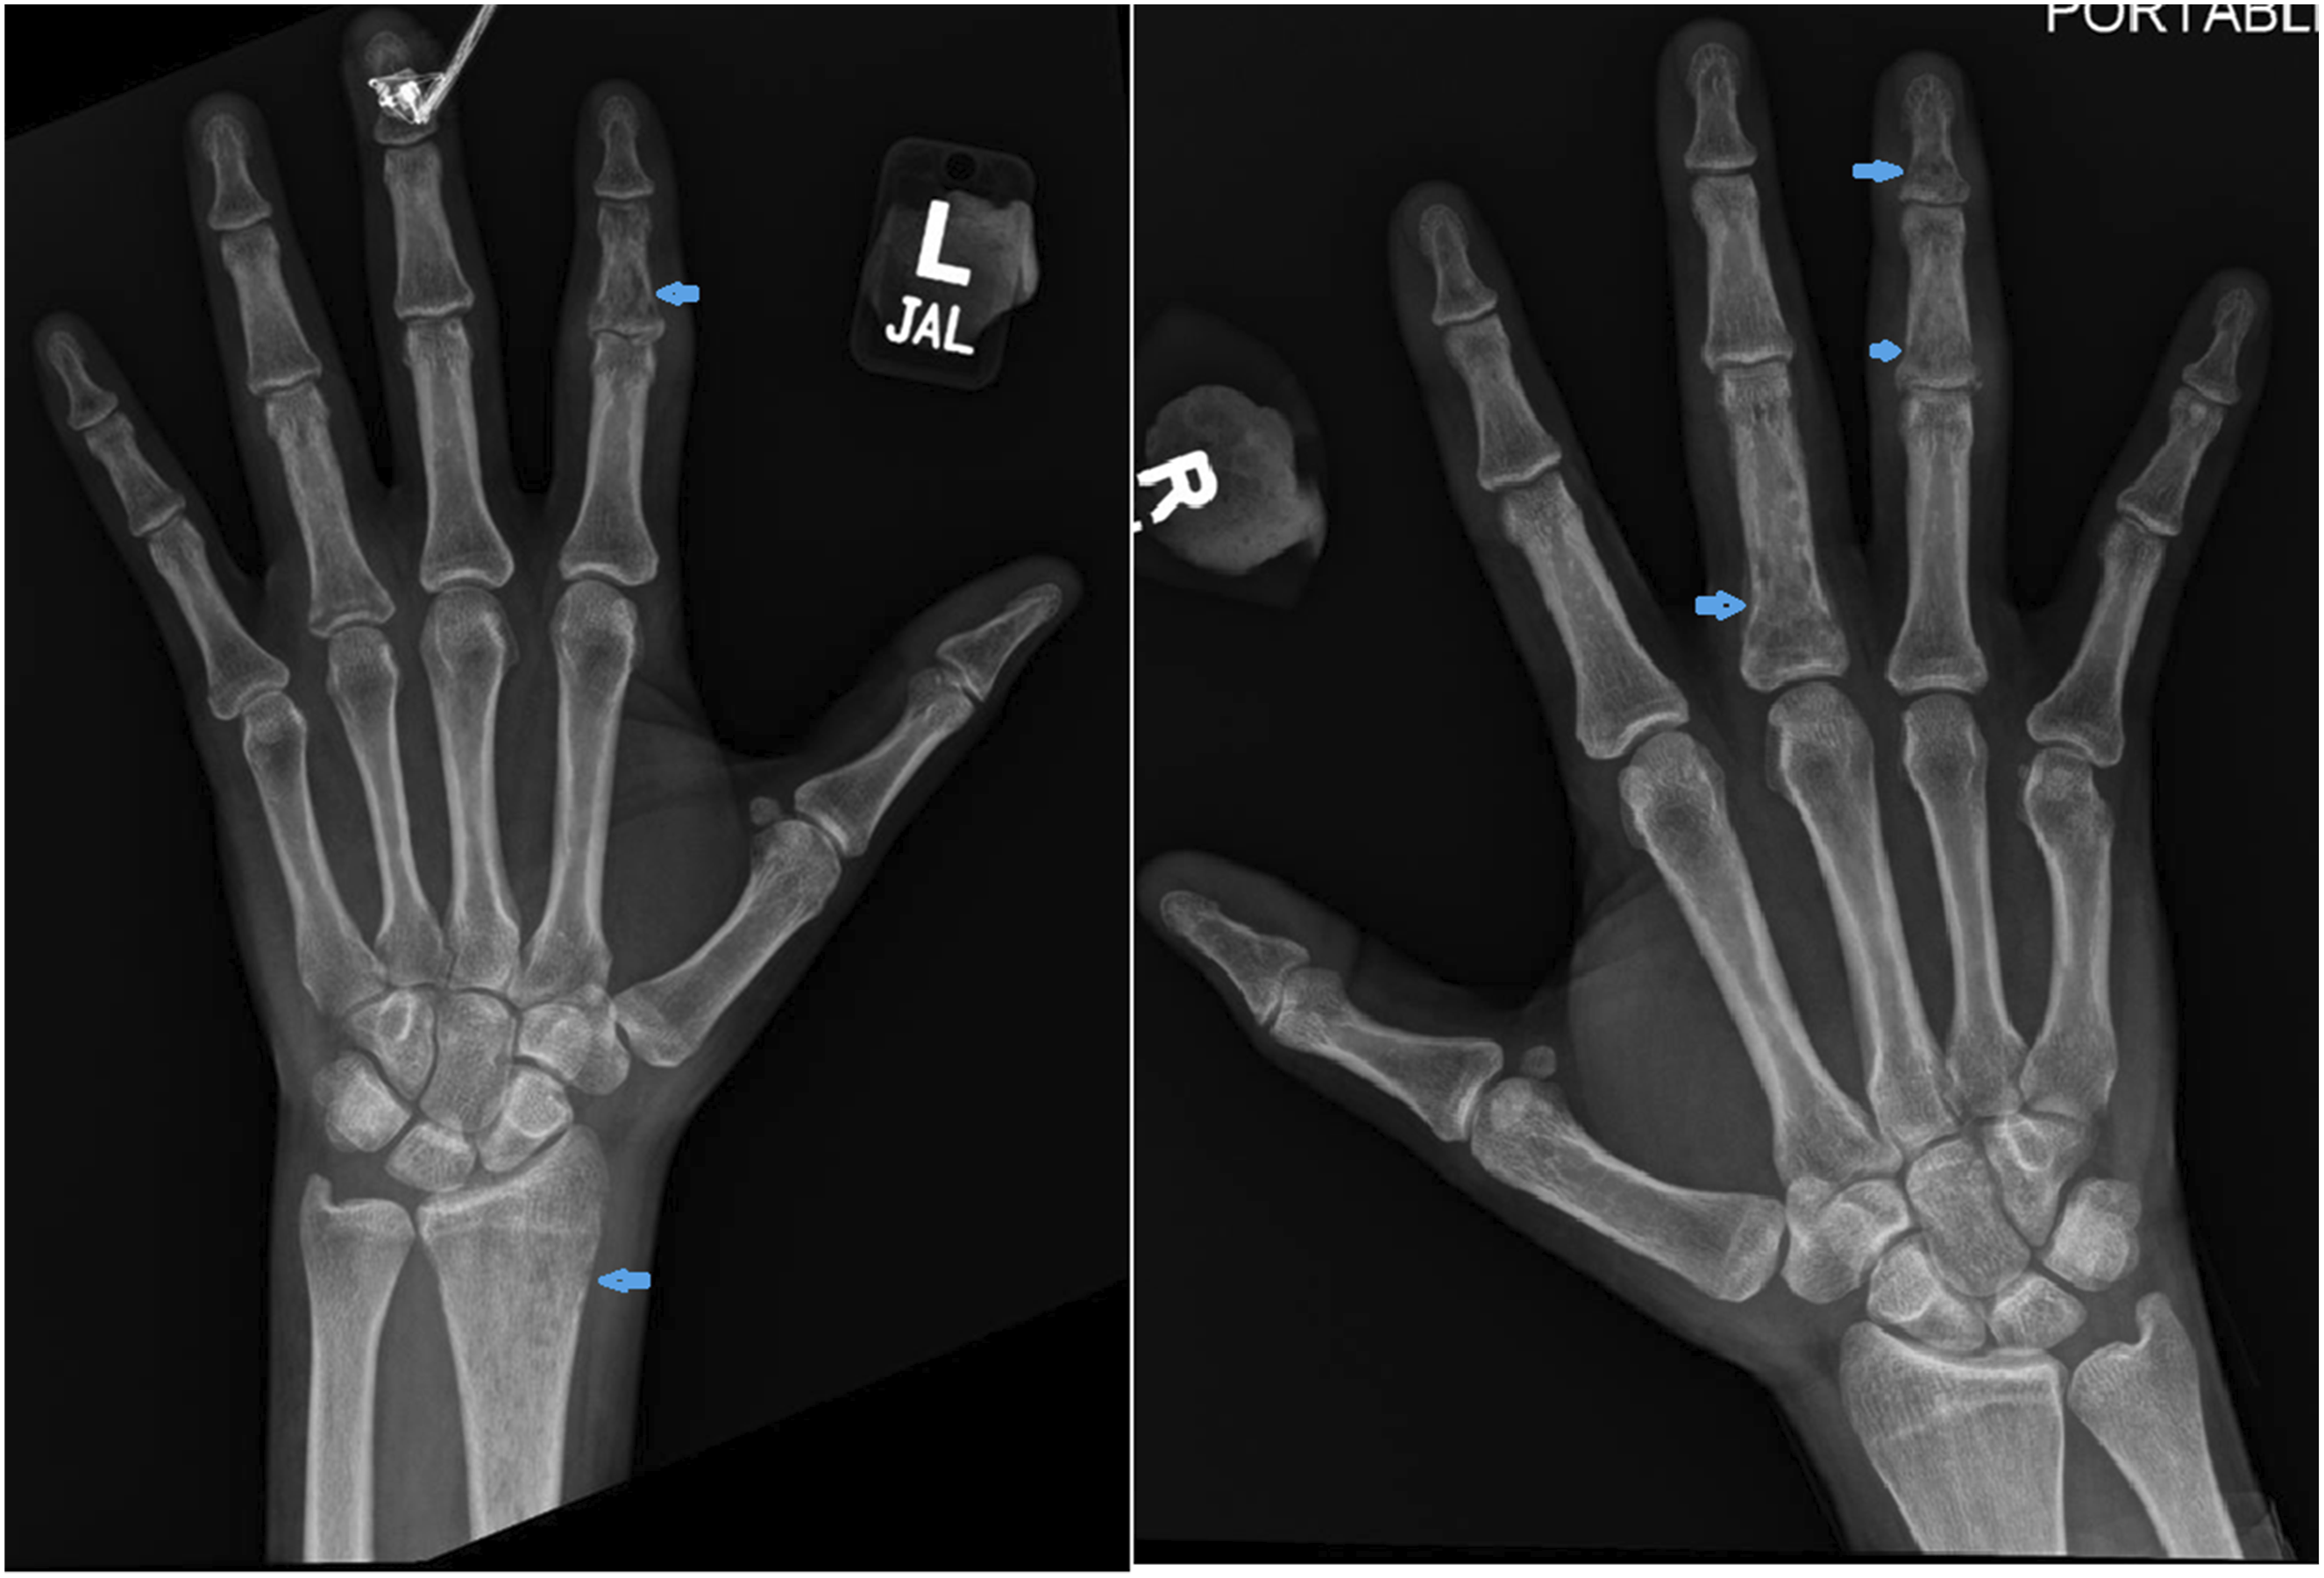

Two months later, he developed new-onset migratory polyarthritis involving the left elbow, bilateral ankles, knees, and small joints of both hands. At this time, the patient did not have any abdominal symptoms. Physical examination revealed joint swelling and tenderness. Radiographs of the right hand (Figure 1) and left elbow (Figure 2) obtained at this time demonstrated only soft tissue swelling, with no radiographic evidence of erosive or inflammatory arthritis, focal bone lesions, or bone infarction. MRI of the left elbow showed posterior subcutaneous and soft tissue edema with associated triceps muscle edema, a small joint effusion and mild bone marrow edema at the olecranon process (Figure 3). Synovial fluid aspirated from the left elbow showed mildly elevated white blood cell count (3000 cells/mm3), but Gram stain, culture, and crystal analysis were negative. Laboratory tests showed elevated ESR and CRP, normal serum uric acid, creatine kinase, and complement (C3 and C4) levels. Antinuclear antibody and rheumatoid factor were negative. Urine tests for Radiographs of the right hand demonstrating soft tissue swelling predominantly about the metacarpophalangeal joints. No osseous erosions, no focal lytic or sclerotic bone lesion. Radiographs of the left elbow demonstrating mild soft tissue swelling at the posterior elbow. No osseous abnormalities. Axial STIR MR images of the left elbow demonstrate subcutaneous edema, triceps muscle edema, small joint effusion and mild bone marrow edema at the olecranon process.

Radiographs of the hands revealed multifocal permeative lucencies involving the distal radius and multiple phalanges (Figure 5), raising concern for systemic arthropathy or osteomyelitis. MRI of the hands showed bone marrow signal abnormalities consistent with multiple bone infarcts (Figures 6–8). Radiographs of the hand showing permeative lytic lesions involving left distal radius and multiple phalanges (blue arrows). (a) Coronal T1W and (b) Coronal STIR MRI of the right hand reveals bone infarcts at the scaphoid and middle finger proximal phalanx. (a) Coronal T1W and (b) STIR MRI of the left hand demonstrates patchy T1 hypointense signal and STIR hyperintense signal abnormality at the distal radius representing ischemic changes. (a) Coronal T1W, (b) Coronal STIR, (c) Axial STIR, and (d) Post contrast T1FS of the left hand demonstrates bone infarct at the ring finger proximal phalanx, and soft tissue edema and enhancement.